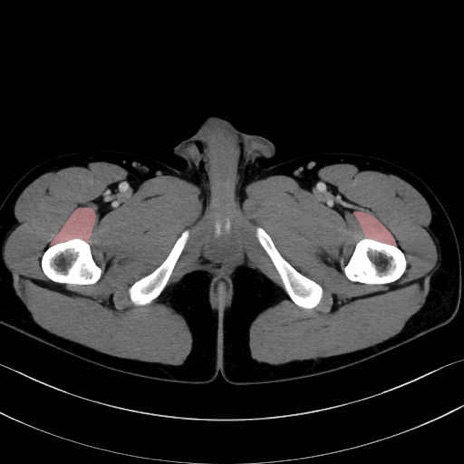

中間広筋 (Vastus intermedius)